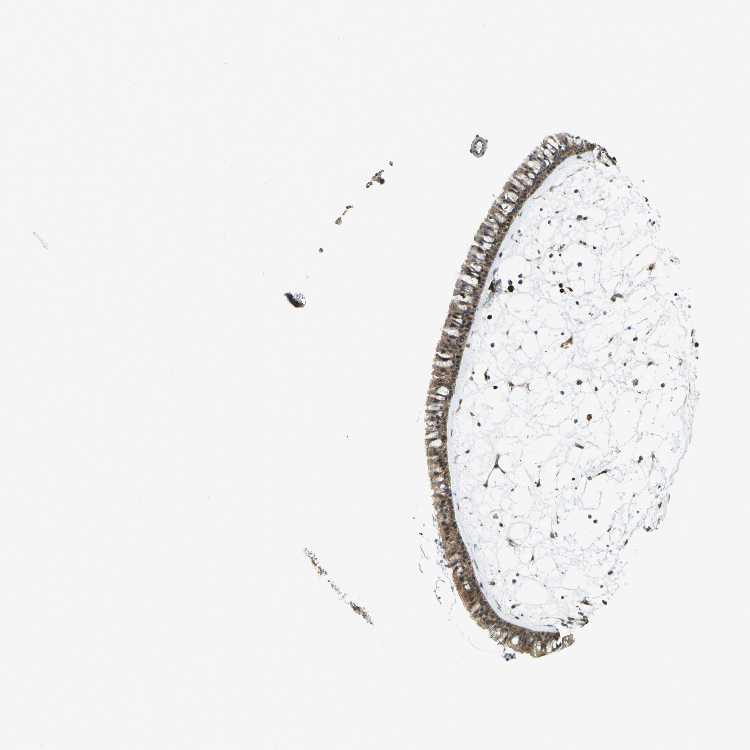

TISSUE PRIMARY DATA NASOPHARYNX Show tissue menu

Nasopharynx

NASOPHARYNX - Antibody stainingi

Antibody staining in the annotated cell types in the current human tissue is reported as not detected, low, medium, or high, based on conventional immunohistochemistry profiling in selected tissues. This score is based on the combination of the staining intensity and fraction of stained cells.

Each image is clickable and will lead to virtual microscopy that enables deeper exploration of all samples and also displays staining intensity scores, fraction scores and subcellular localization as well as patient and tissue information for each sample.

Antibody HPA026918Antibody CAB013274Antibody CAB018389

Respiratory epithelial cells MediumMediumMedium